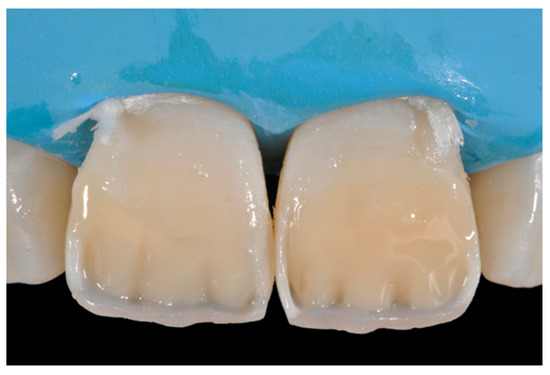

Figure 13.

Vertical and horizontal anatomy outlined with a pencil. Reprinted from Restauri diretti nei settori anteriori, G. Paolone, S. Scolavino, © 2021, with permission from Quintessence Publishing Italy.

Figure 14.

After vertical and horizontal anatomy definition and final polishing. Reprinted from Restauri diretti nei settori anteriori, G. Paolone, S. Scolavino, © 2021, with permission from Quintessence Publishing Italy.